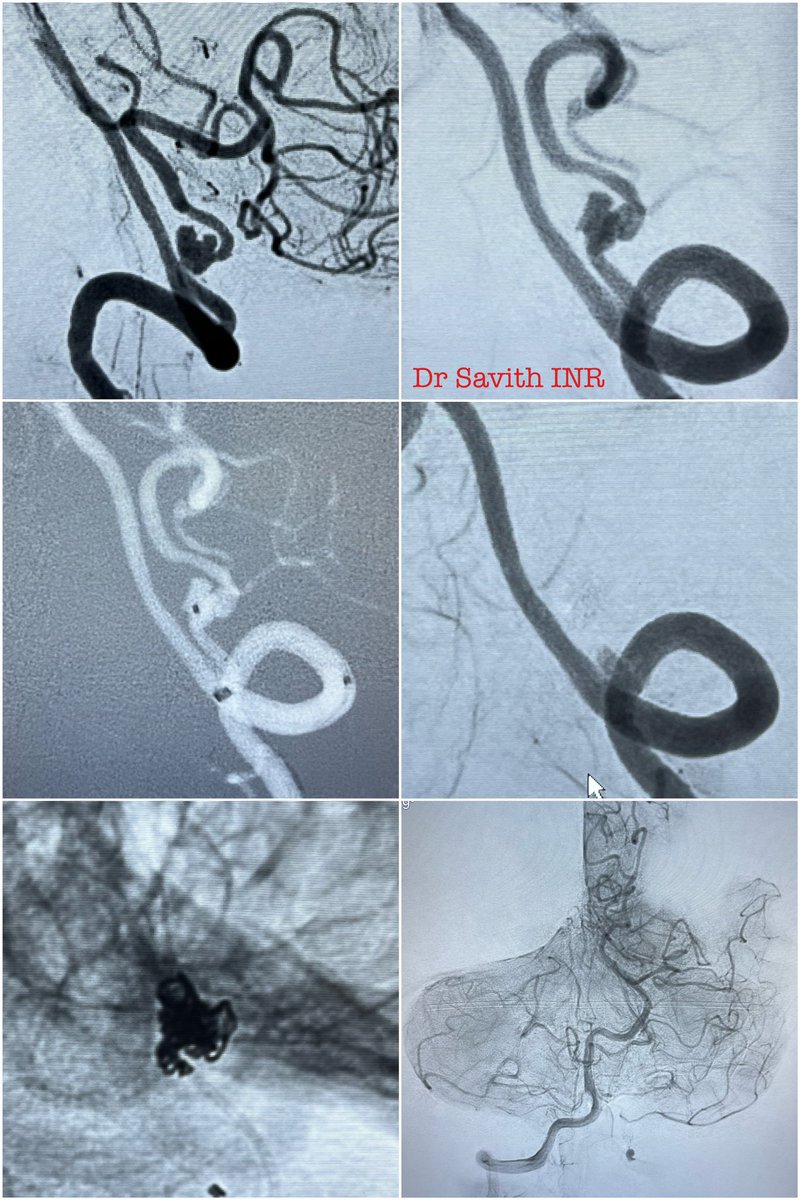

60 year old female with SAH and hydrocephalus from ruptured left PICA dissecting aneurysm. Partent artery occlusion done followed by EVD. Follow up CT showed left PICA territory infarct. Neurological stable. #aneurysm #neurointervention #coiling